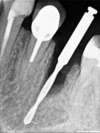

La sortie la tête implantaire de cicatrisation est faite 4 mois après.

La connectique interne est bien visible et la gencive est saine.

Le pilier est transvissé

Et une couronne provisoire est mise en attente de la définitive (suivant la demande de la patiente).

La reconstitution osseuse a permis la pose de l'implant

- Il n'est pas nécessaire aujourd'hui d'avoir recour à des greffes osseuses par prélèvement, un comblement d'os synthètique est bien mieux tolèré et donne d'excellents résultats.